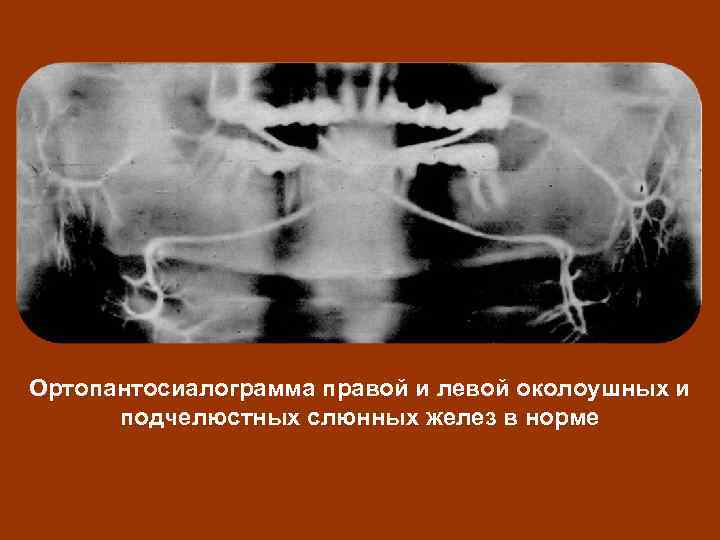

Ортопантосиалограмма правой и левой околоушных и подчелюстных слюнных желез в норме

Ортопантосиалограмма правой и левой околоушных и подчелюстных слюнных желез в норме